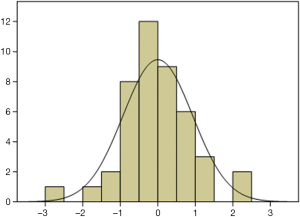

According to the standardized residuals histogram, the standardized residuals of these measurements were normally distributed (Figure 2). According to the normal P-P plot of regression standardized residual, the points in the graph were basically located in one straight line. Thus, the equation was proven to be statistically significant (Figure 3).

Our study also found that pleural effusion at an amount of 500–1,000 mL was significantly correlated with the maximum depth and maximum thickness at the subscapular line but not with the maximum depths at other lines. In contrast, Shen et al. found that the pleural effusion amount was positively correlated with the maximum depth under US but was not significantly correlated with the number of rib spaces, number of longitudinal zones, and sequence of drainage (14). The maximum thickness was employed as a coefficient in our equation because the maximum depths at all these five lines showed no statistical significance in patients with a pleural effusion amount of smaller than 500 mL or between 500 and 1,000 mL. In addition, we divided the actual pleural effusion amount into three groups to make the estimation results more accurate. According to the standardized residuals histogram, the standardized residuals of these measurements were normally distributed, which demonstrated the statistical significance of the equation. Our study was limited by its relatively small size. Also, the actual pleural effusion amount affects the depth of US measurement. If the pleural effusion amount is too small or too large, the measurement for the depth will yield an accurate result, which further affects the accuracy of the equation. Further study is warranted to confirm whether the US measurement equation is feasible for patients with a small/large amount of pleural effusion.